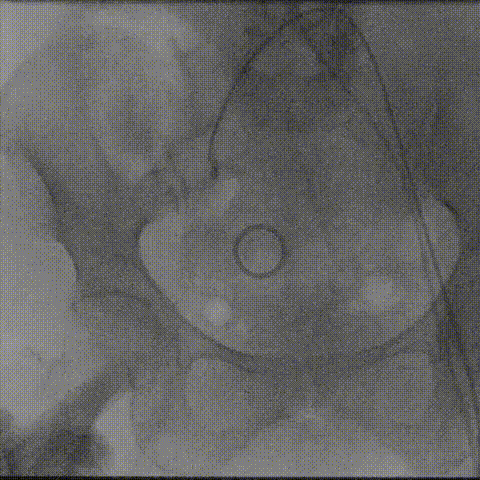

超声影像:

20mm球囊后扩后支架腰部形态接近理想膨胀状态,瓣周漏微量。

植入后血流动力学有效改善,术后Vmean 1.06m/s Pgmean 6mmHg。